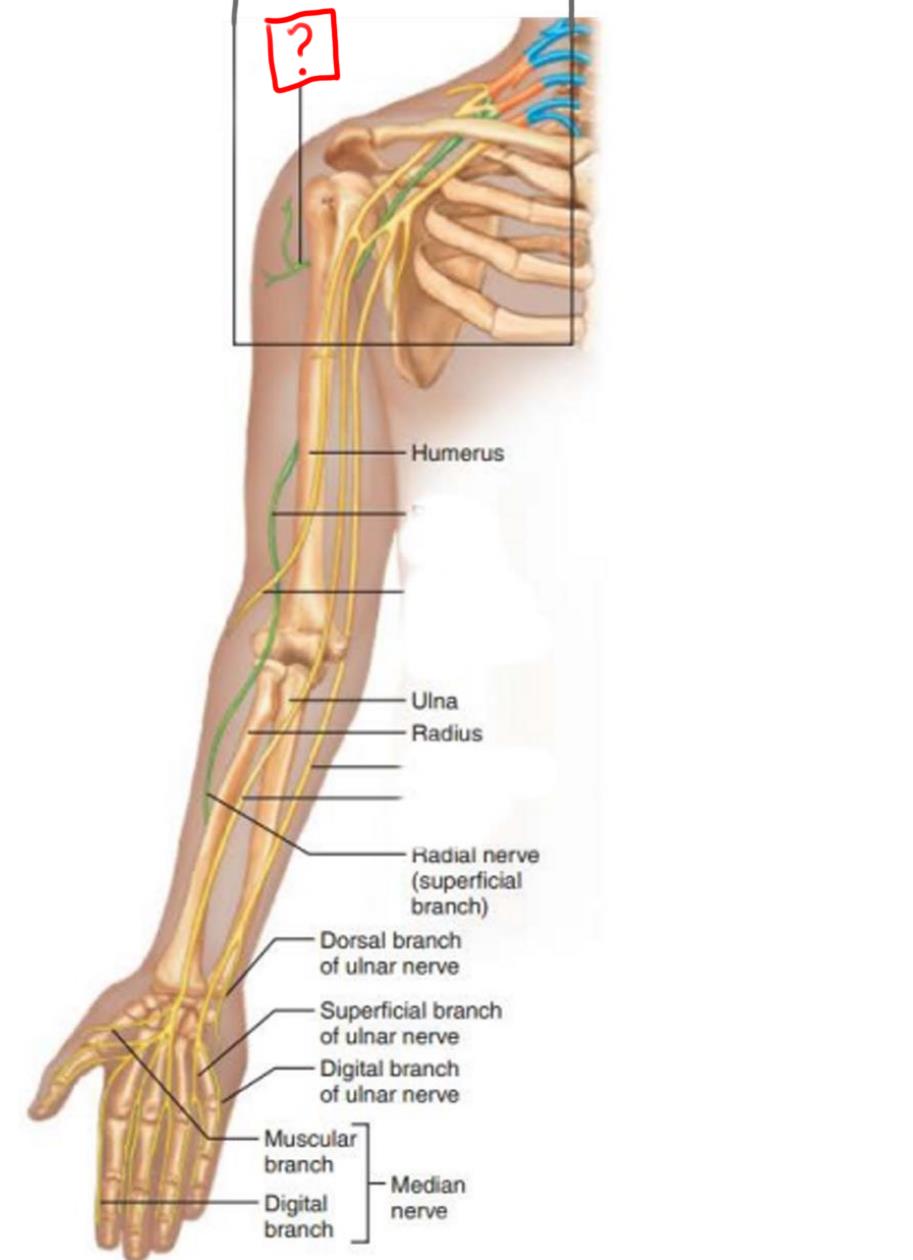

radial nerve

ulnar nerve

median nerve